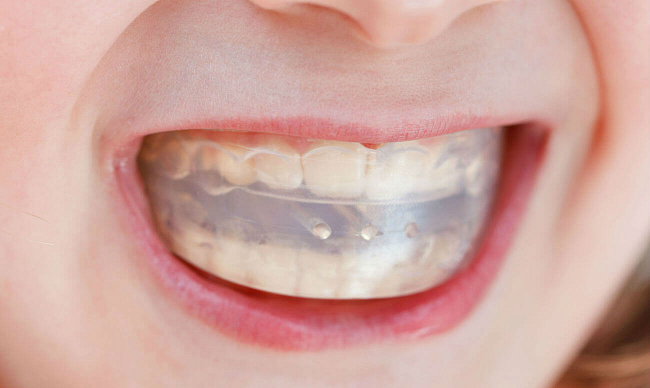

Дезокклюзией называется разобщение окклюзионных поверхностей. Метод состоит в том, что на область дефекта устанавливается ортодонтическая или протезная конструкция с накусочной площадкой напротив выдвинувшихся зубов.

При их контакте остальные зубы оказываются разобщенными со своими антагонистами, и вся нагрузка приходится на выдвинутые зубы, вызывая их интрузию (углубление в десну).

Метод дезокклюзии применяется при 1-ой форме феномена у пациентов не старше 40 лет. Толщина накусочной площадки выбирается индивидуально, на ее выбор влияет высота нижней 1/3 лица пациента. Толщина площадки должна быть такой, чтобы расстояние между остальными зубами при их разобщении было не больше 2 мм.

Ношение аппарата продолжается до момента, когда остальные зубы начинают контактировать со своими антагонистами.

Если смещение зубов на 2 мм недостаточно, коррекцию проводят поэтапно. После вступления интактных единиц в контакт со своими антагонистами, накусочную площадку повышают 2-х миллиметровым слоем самополимеризующейся пластмассы.

Каждый этап коррекции снижает высоту выдвинувшихся зубов на 2 мм. Наращивание накусочной площадки проводят столько раз, сколько требуется для возвращения выдвинувшихся зубов в их нормальное положение.

После этого для дефектного ряда изготавливается постоянный протез. Длительность лечения обуславливается степенью деформации, длиной дефекта, состоянием пародонта, возрастом пациента.